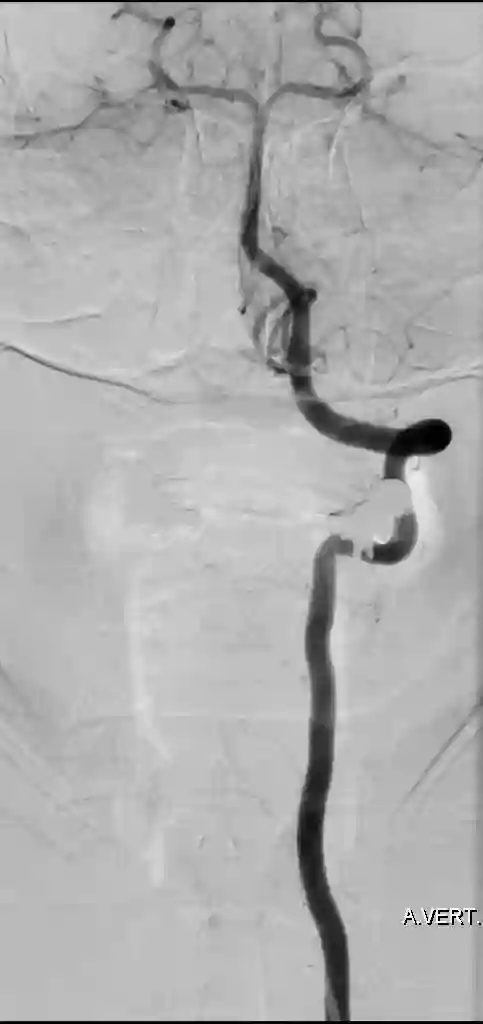

Abbildung

Bildgebung

Der Goldstandard zur optimalen Darstellung der Arteria vertebralis ist die digitale Subtraktionsangiographie, kann jedoch je nach klinischer Fragestellung auch in der CT-Angiographie oder MRT Bildgebung dargestellt wird.

Im Bereich der Arteria vertebralis können typischerweise Dissektionsaneurysmen auftreten und eine Subarachnoidalblutung verursachen[^3]. Die Behandlung dieser Dissektionsaneurysmen kann je nach Fall beispielsweise endovaskuläre mithilfe von Implantation eines Flow-Diverters behandelt werden[^4] [^5].